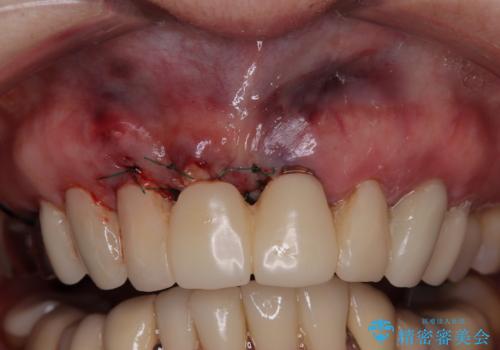

前歯のインプラントは埋入されたポジションが望ましい位置ではなく、インプラントを活用して段差を回収することは不可能と判断し、歯肉移植によりインプラントを隠して、ブリッジにて歯肉ラインを整えることとしました。

- 外科手術のため、術後に出血、痛みや腫れ、違和感を伴います